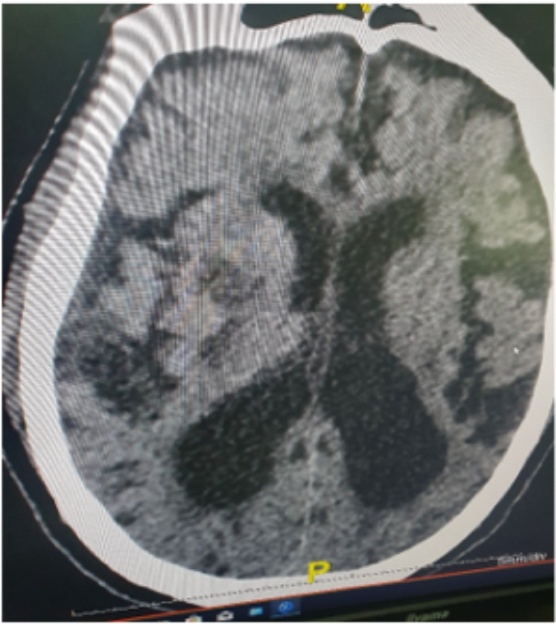

Ischemic stroke was predominant, accounting for 83.3% represented by Figure 1 of cases, consisting mainly of lacunar infarcts and established ischemic strokes, most often located in the superficial or deep Sylvian territory represented by Figure 2. Haemorrhagic lesions accounted for 16.7% and were often distributed as capsulolenticular and capsulothalamic haematomas. Shown in Table 2.

Figure 2. Left capsulo-thalamic hyperdensity surrounded by perilesional oedema and ventricular contamination suggestive of haemorrhagic stroke.

On CT scans, Sylvian lacunar ischaemic strokes predominated, which was practically similar to the results observed in Côte d’Ivoire [11]. Haemorrhagic strokes consisted mainly of intraparenchymal haematomas, preferentially located in the capsulo-lenticular or capsulo-thalamic regions.

Strokes remain a daily concern in the Central African Republic, as in other African countries. In this study, computed tomography improved the diagnosis of strokes, enabling a better distinction between ischaemic and haemorrhagic strokes and identifying the topography of the lesions. The vast majority of these strokes were ischaemic in nature, occurring in the superficial or deep Sylvius territory. Haemorrhagic lesions were dominated by intraparenchymal haematomas, preferentially capsulo-lenticular or capsulo-thalamic.